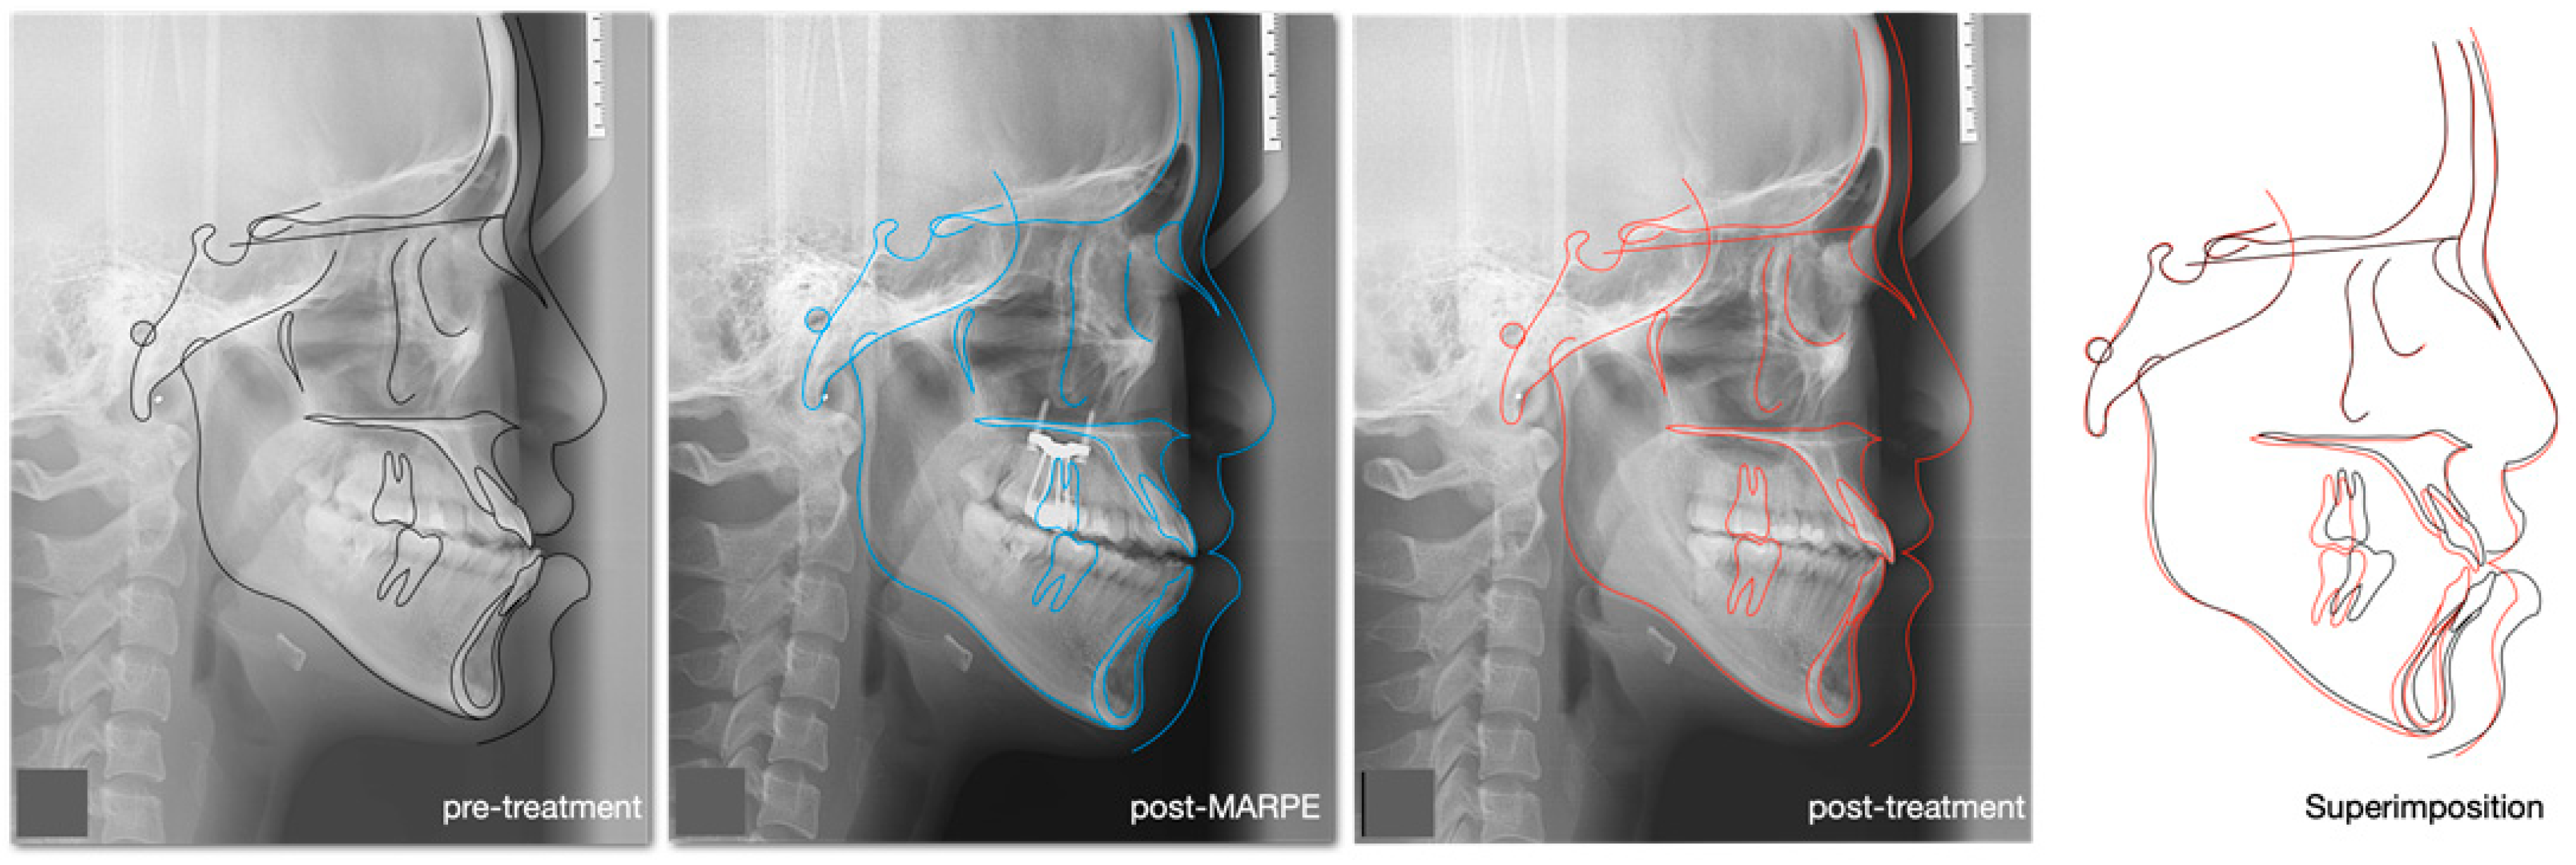

2.4. Treatment Progress

2.5. Treatment Results